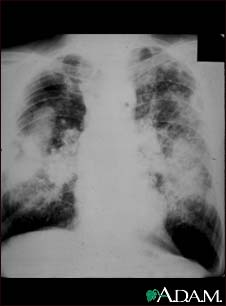

Coal workers pneumoconiosis, complicated #2

This picture shows complicated coal workers pneumoconiosis. There are diffuse, massive light areas that run together in the upper and middle parts of both lungs. These are superimposed on a background of small and poorly distinguishable light areas that are diffuse and located in both lungs. Diseases which may explain these X-ray findings include, but are not limited to: complicated coal workers pneumoconiosis (CWP), silico-tuberculosis, and metastatic lung cancer.